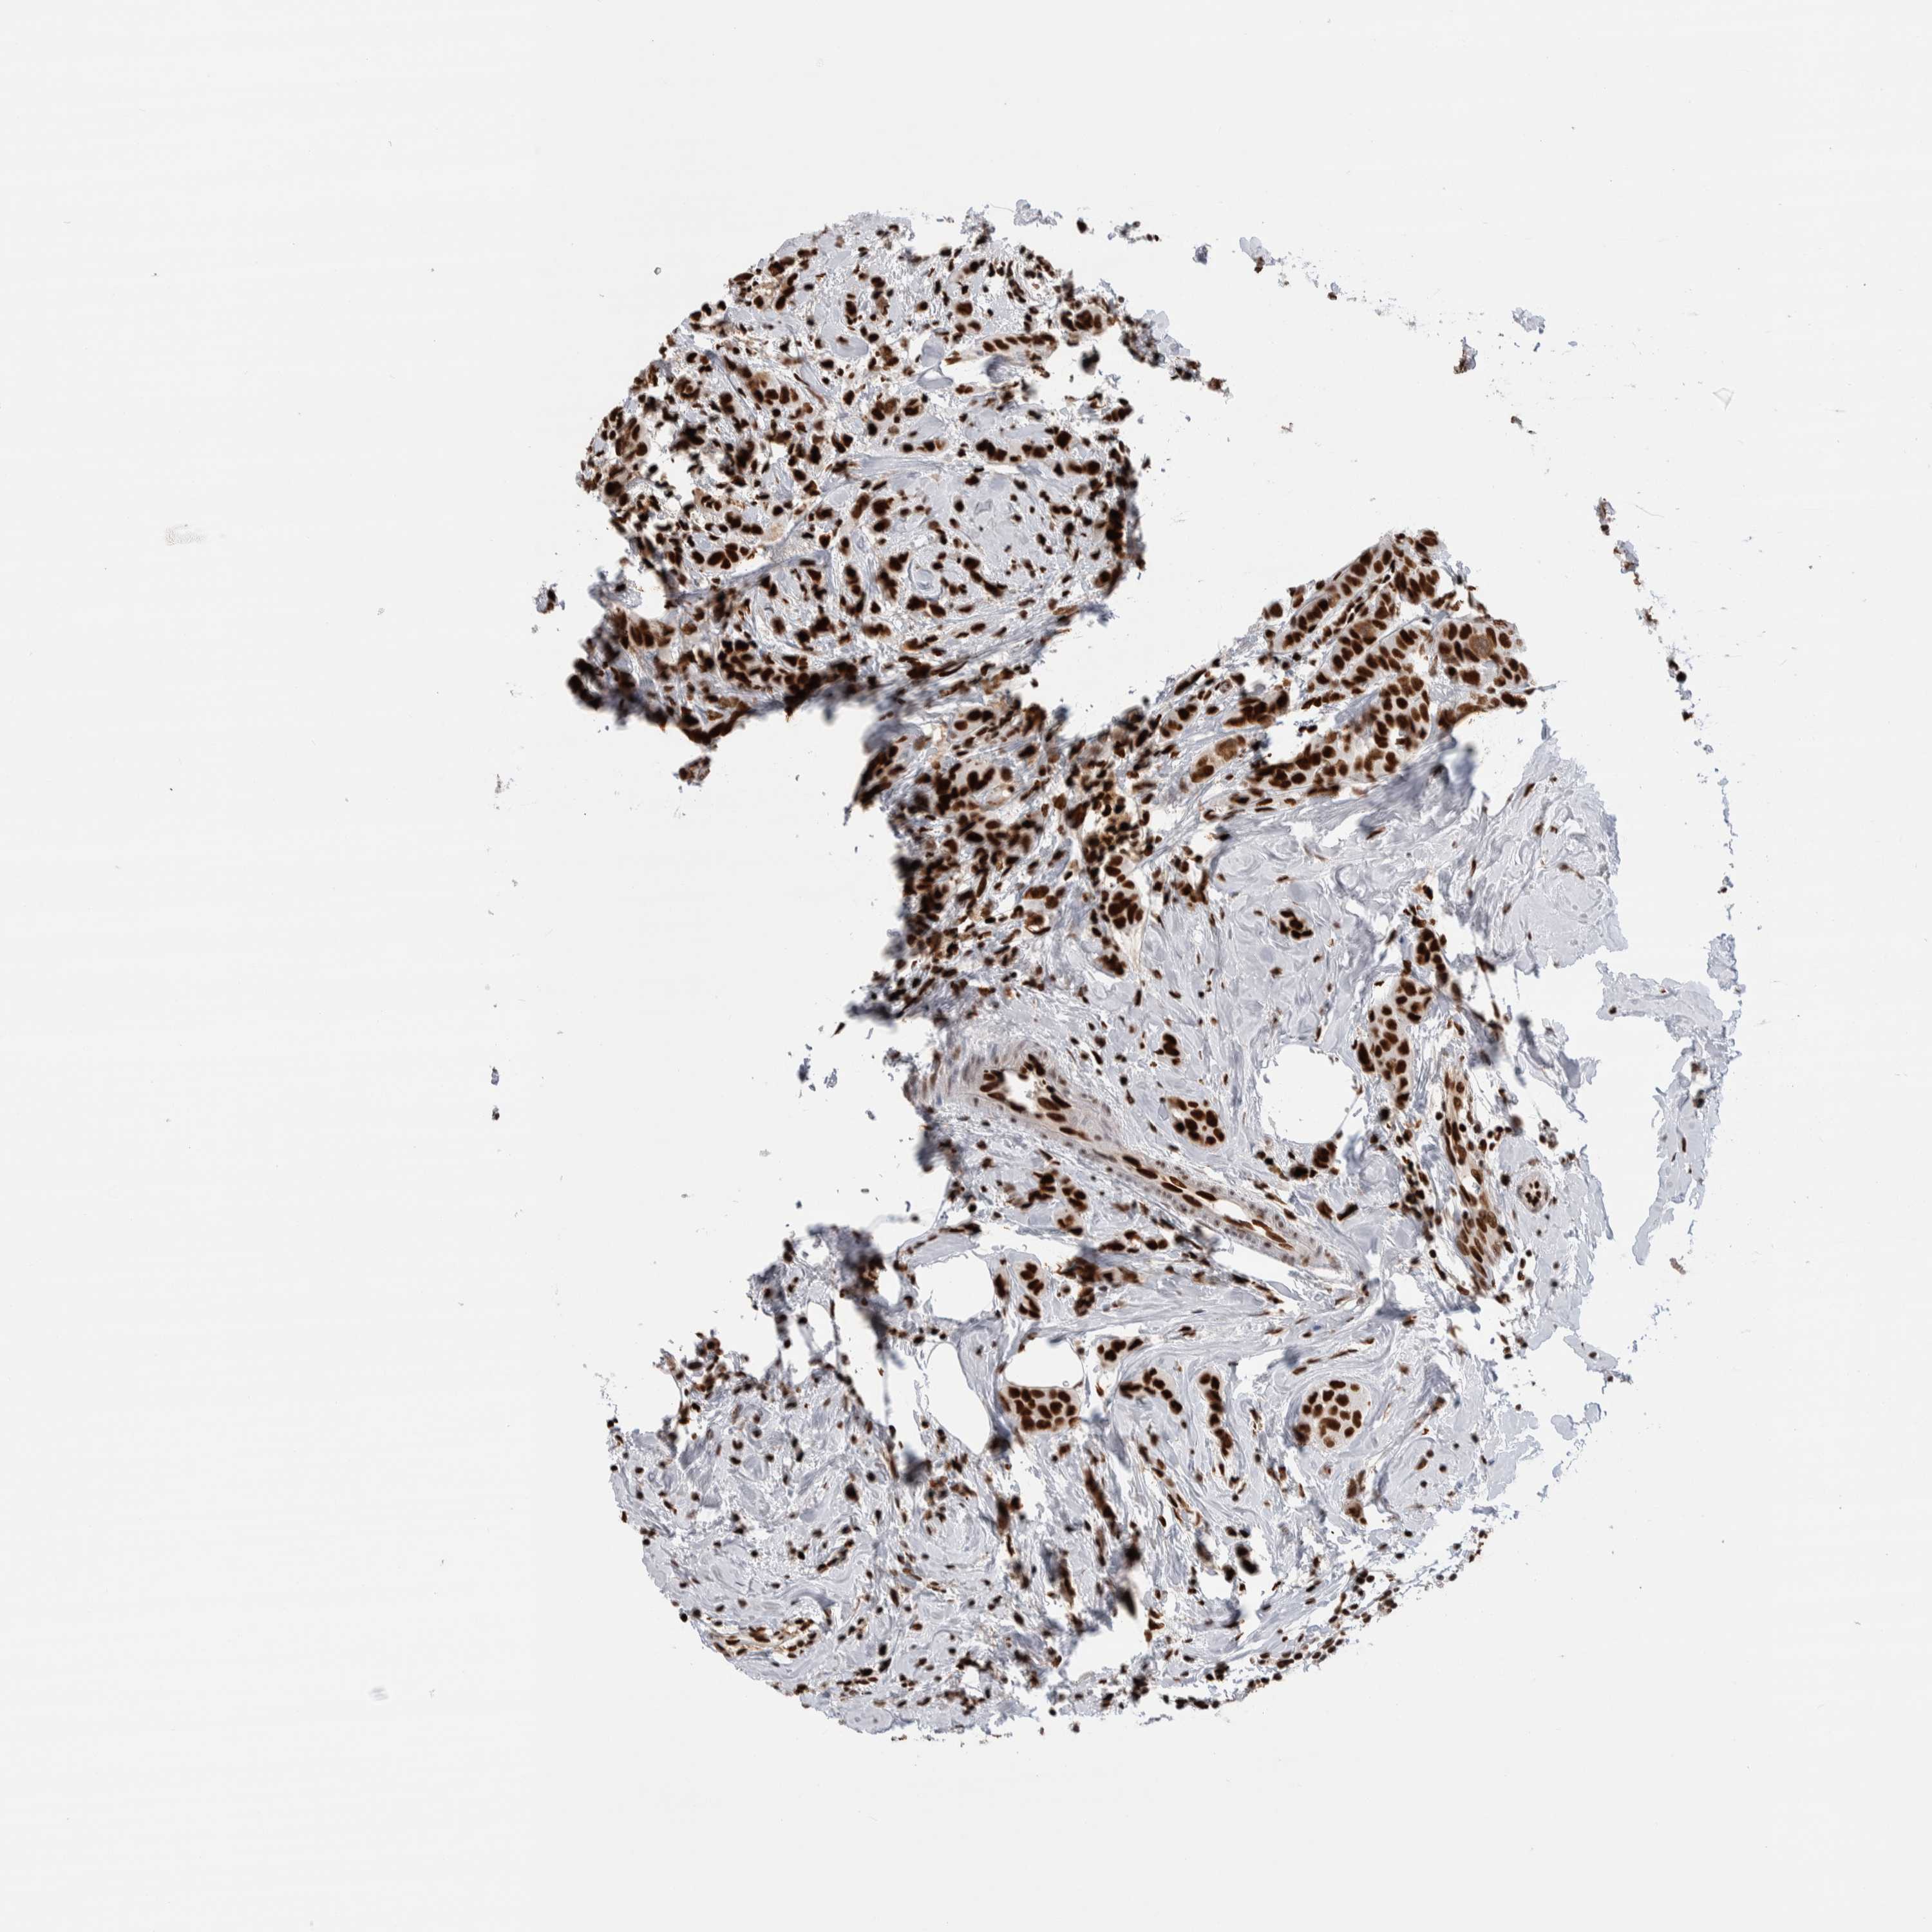

BRCA TCGA BRCA VALIDATION PROTEIN EXPRESSION